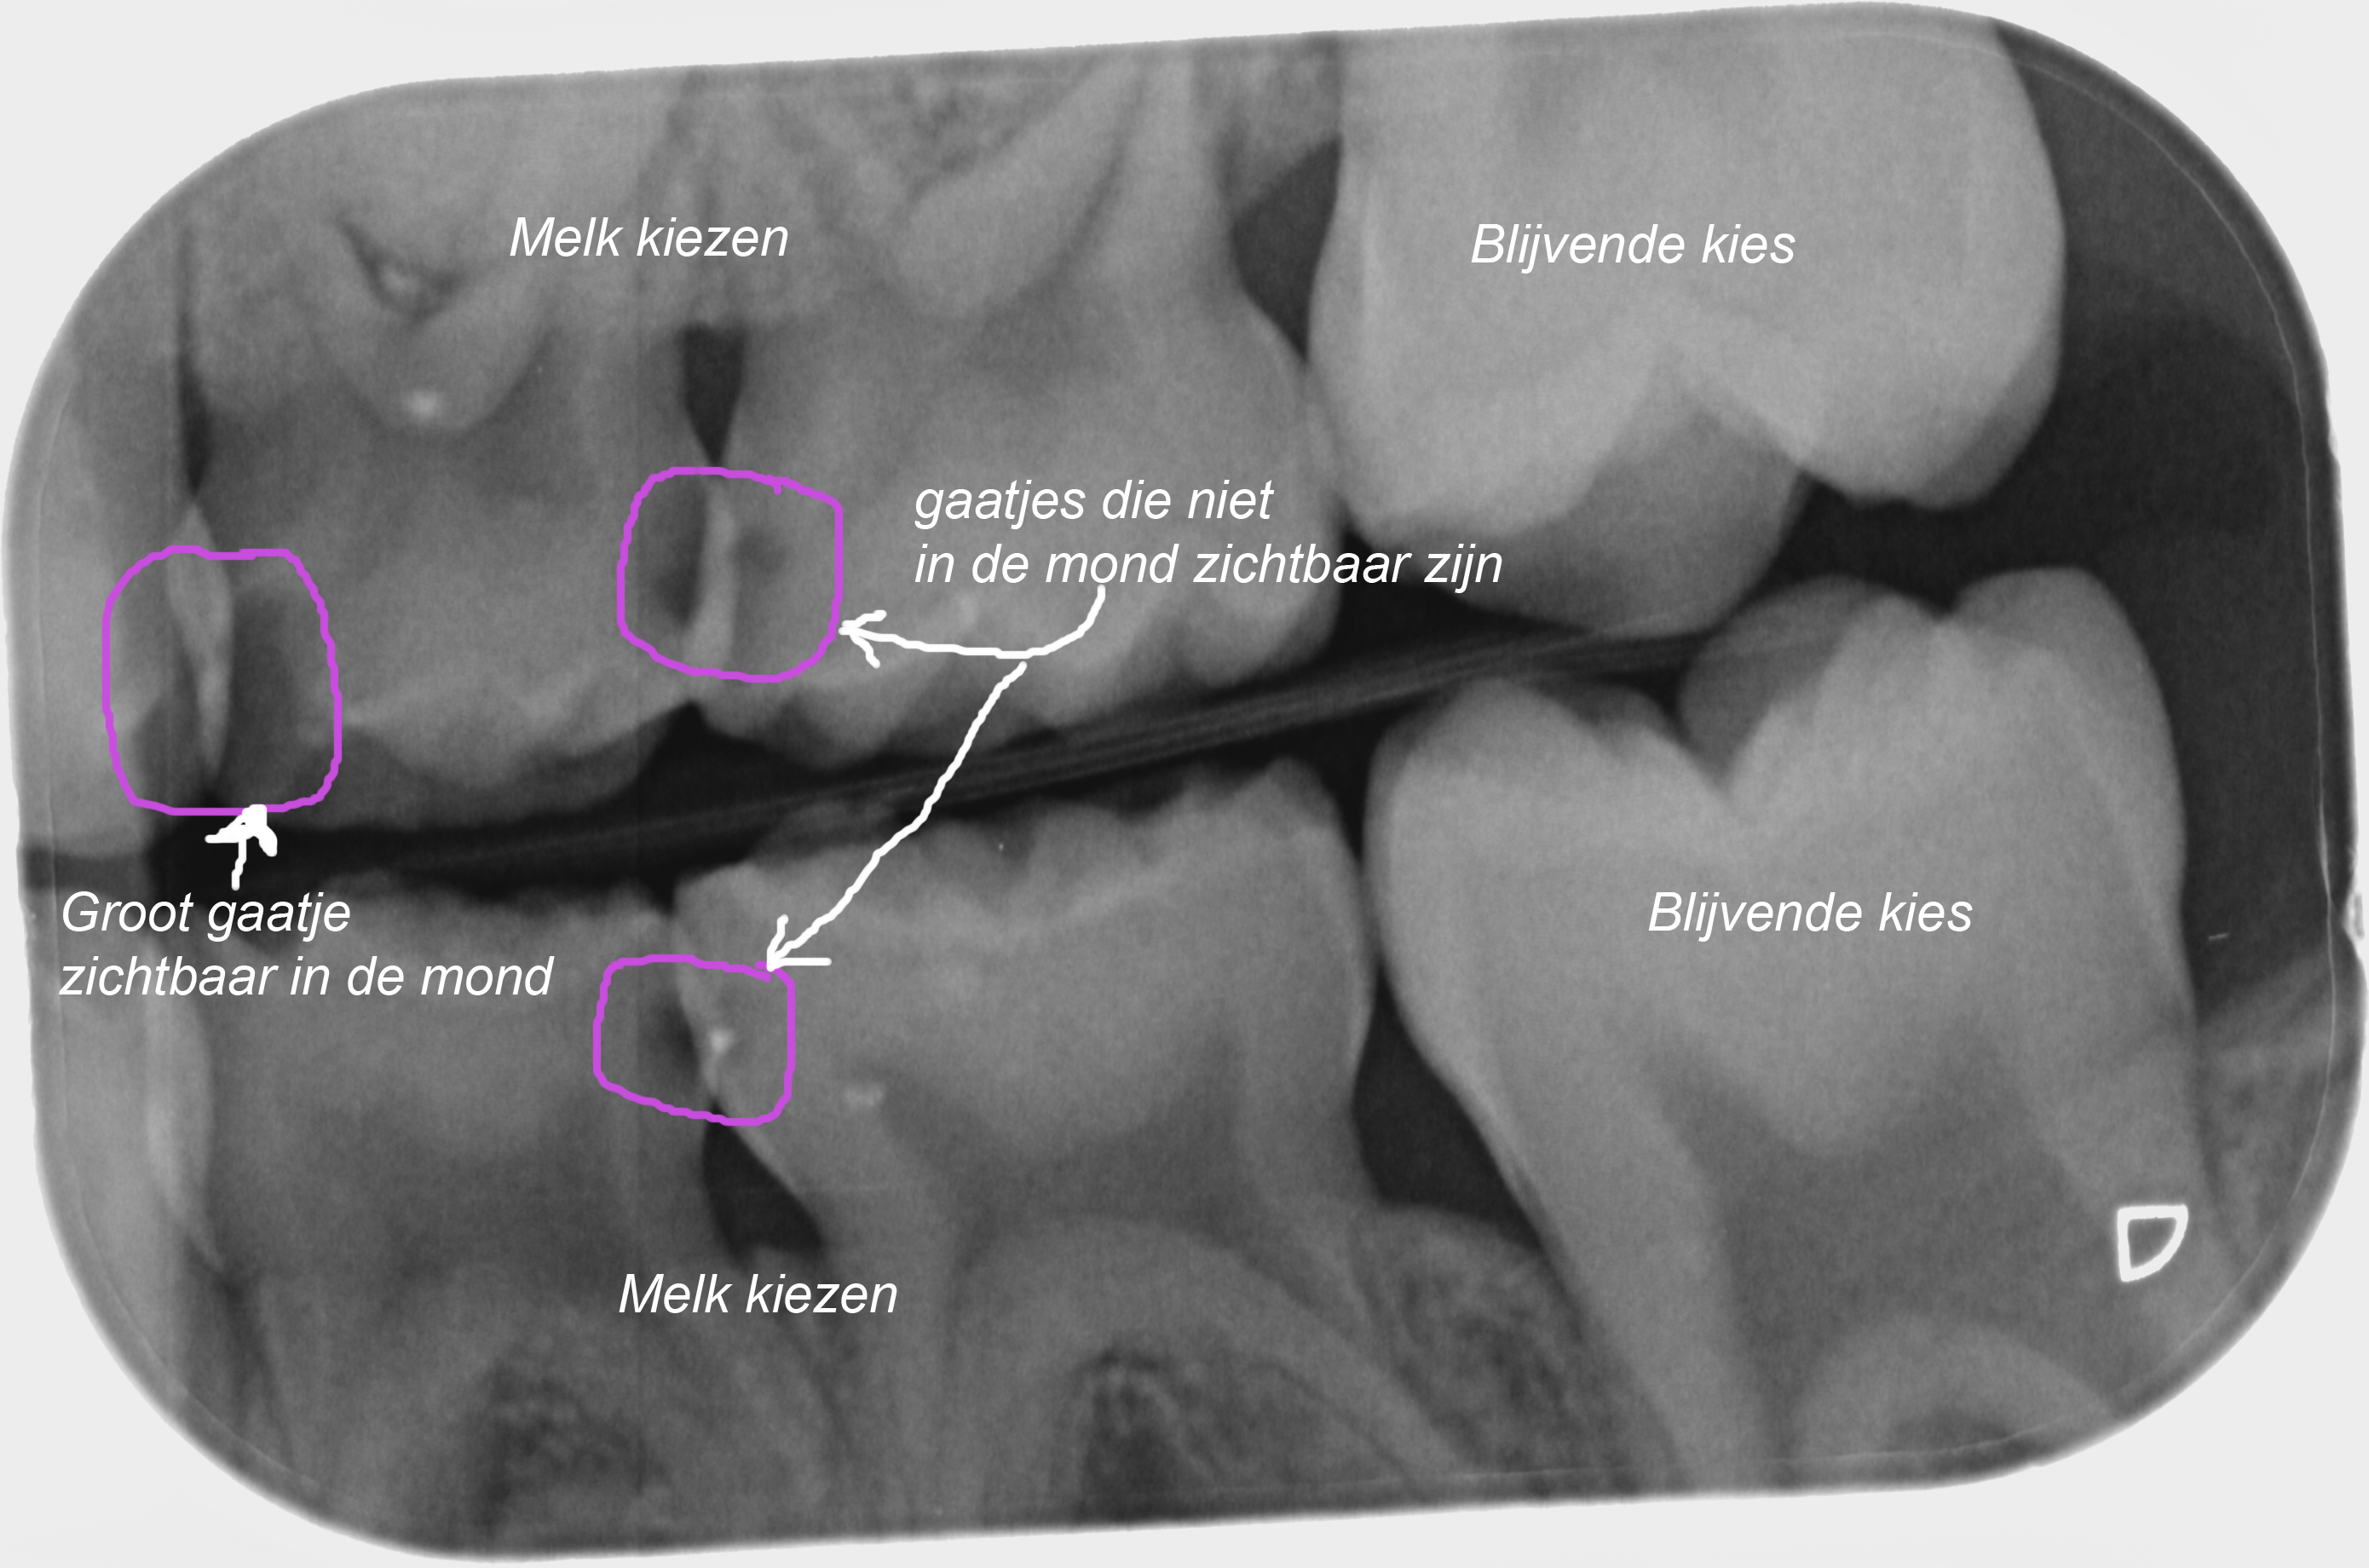

Kindertandarts Landsmeer | Mondhygienist Een gaatje komt nooit alleen

Dokkum Tandarts - K I N D E R K R O O N - Wanneer kinderen gaatje hebben is het beter om de tand of kies te laten zitten. Wanneer

Hoe ziet een gaatje eruit? Zo herken je in de tanden en kiezen!

Gaatjes?? | Forum